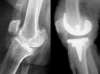

The primary total knee replacement consists of replacing the articular surfaces of the knee joint for the first time, which is in a knee that has never been implanted before the index operation. This is sort of a resurfacing concerning the femoro-tibial joint and, more inconstantly, the patello femoral joint.